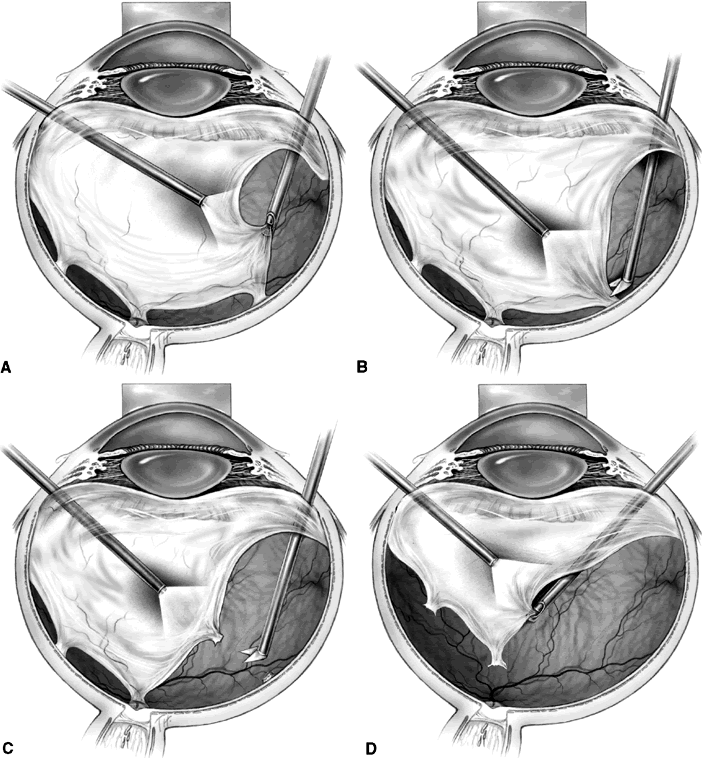

“EN BLOC” VITRECTOMY AND MEMBRANE EXCISION

The en bloc technique uses the anteroposterior traction of the vitreous to elevate the edge of the fibrovascular membrane, thus serving as a “third hand.” Removal of the formed vitreous is delayed until the end of the membrane removal. Initially, the vitrectomy cutter is used to create a tunnel through the formed vitreous from the sclerotomy site to an area of vitreoretinal separation (Fig. 3A). Any subhyaloid blood then is removed through this opening. The remaining posterior vitreous surface is left attached and assists in visualizing epicenters of adhesion between fibrovascular tissue and the retina (see Fig. 3B). An illuminated pick may be used to further elevate the fibrovascular tissue, and horizontal scissors are used to amputate epicenters of fibrovascular vitreoretinal adhesion (see Fig. 3C). Hemorrhage may occur when these epicenters are cut, but since the vessels are cut close to their origin, the bleeding usually is minimal and stops spontaneously. After the posterior vitreous surface and the entire fibrovascular membrane are freed from the retina, they are removed using the vitrectomy probe (see Fig. 3D). The main disadvantage of this technique is an increased risk of iatrogenic peripheral retinal breaks caused by traction at the vitreous base, which may occur in up to 35% of cases.13 Should peripheral retinal breaks occur, they are treated with laser photocoagulation and a longacting intraocular gas tamponade, with or without scleral buckling, depending on break location and surgeon preference.

Fig. 3. A. The vitrectomy cutter is used to create a tunnel through the formed vitreous to an area of vitreoretinal separation. B. The remaining posterior vitreous exerts traction on the epiretinal membrane, assisting in visualization of epicenters of adhesion. C. Horizontal scissors are used to amputate the fibrovascular adhesion at the retinal surface. D. The posterior vitreous surface and the entire fibrovascular membrane have been freed from the retina and are removed using the vitrectomy probe.